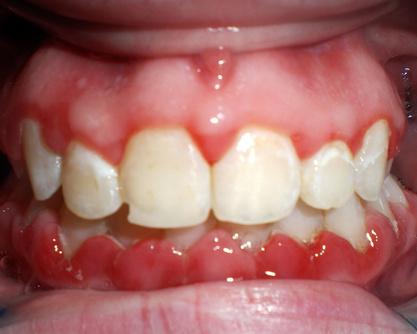

"I love seeing the results of smile makeovers. We've had several people unable to get a job, find a girlfriend, or simply feel generally bad about themselves or their appearance due to their teeth.

When we perform smile makeovers, it changes the patient’s whole demeanor and life immediately after the procedure."

"I love seeing the results of smile makeovers," he shared. "We've had several people not be able to get a job, find a girlfriend, or just feel generally bad about who they are or how they look because of their teeth. When we perform smile makeovers, they just change the patient’s whole demeanor and life immediately after the procedure."